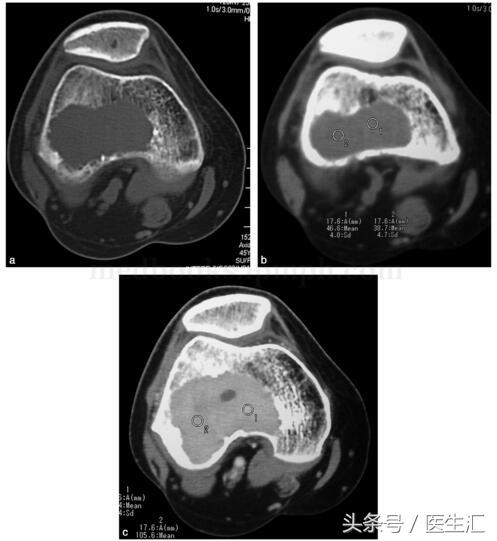

影像學(xué)檢查:X 線示右股骨遠(yuǎn)端骨端發(fā)生的一個(gè)偏心、基質(zhì)均勻、皮質(zhì)膨脹、皮質(zhì)無(wú)骨破壞、無(wú)骨膜反應(yīng)、無(wú)軟組織腫塊的溶骨性破壞(圖29‐1a,圖29‐1b)。CT 示右股骨遠(yuǎn)端骨端的溶骨性破壞,基質(zhì)均勻,注射造影劑后,病變強(qiáng)化,CT 值由強(qiáng)化前的40HU 增加到強(qiáng)化后的110HU(圖29‐2a~圖29‐2c)。

圖29‐2

a﹒CT 橫斷面示股骨外髁處溶骨性骨破壞(骨窗);

b﹒CT 橫斷面示股骨外髁處溶骨性破壞,CT 值為46HU(軟組織窗);

c﹒CT 橫斷面示增強(qiáng)CT 示腫瘤強(qiáng)化,CT 值達(dá)105HU